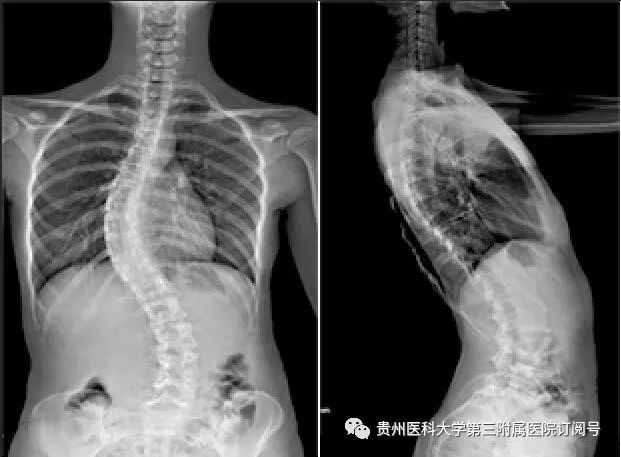

2月22日,杨华、熊永发带领骨科团队为小玲顺利实施了“后路脊柱侧弯矫形手术”。术后,小玲侧弯脊柱得以矫正,身高还增高了约3厘米。

术后全脊柱正侧位片